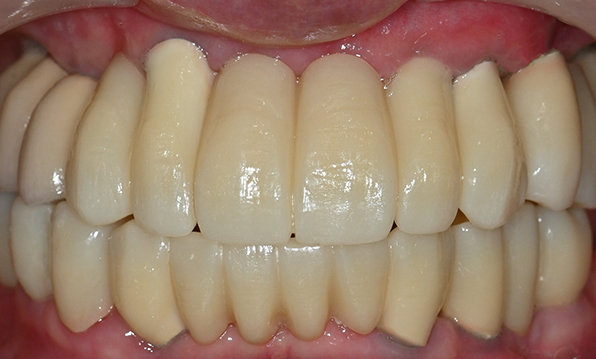

치료기간 : 2021.04.12~2021.09.15